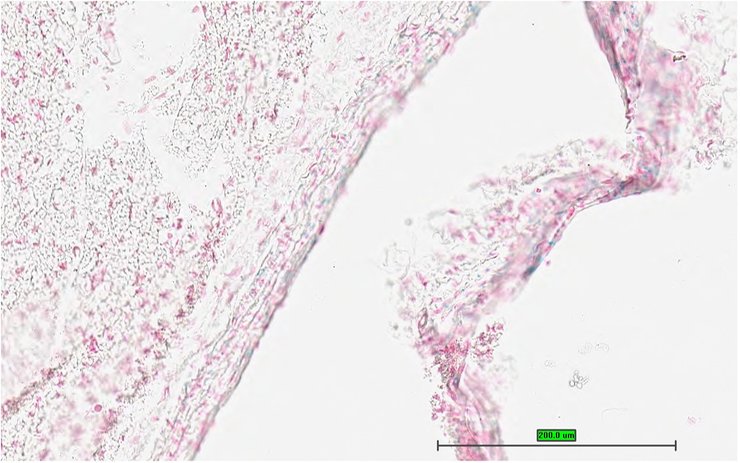

TS28: skin Present UC Davis_1866100

Specimen UC Davis_1866101: postnatal adult; Peli1tm1b(EUCOMM)Wtsi/Peli1+ (more )

Structure Level Pattern Image Note

TS28: skin Present UC Davis_1866101

Specimen UC Davis_1866102: postnatal adult; Peli1tm1b(EUCOMM)Wtsi/Peli1+ (more )

TS28: skin Present UC Davis_1866102